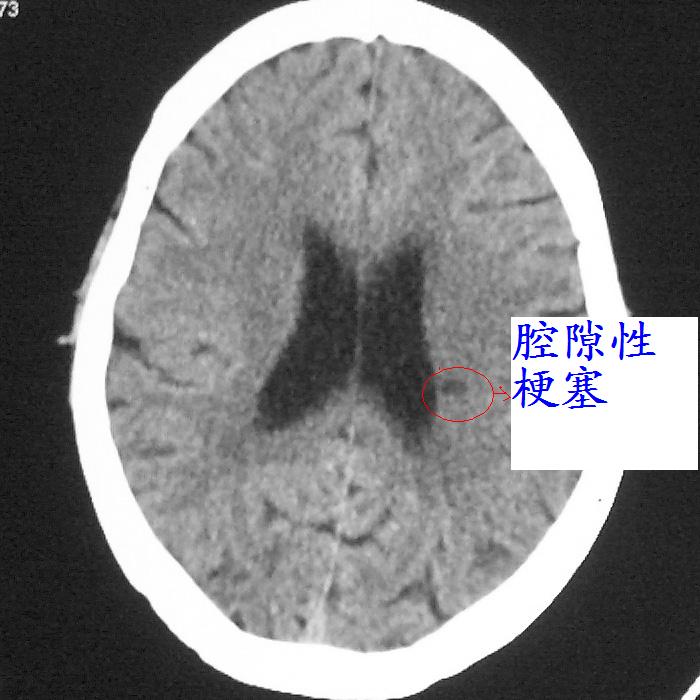

f,70y,口角歪斜、流涎、吐词不清三天

左侧大脑基底节区点状低密度影,边缘清楚,左侧腔梗或软化灶,没什么问题啊?

症状这么明显的话一般不会是单纯面神经麻痹引起的,最好做个mri,如果确实没有问题的话才能考虑面神经麻痹,毕竟这两种病的治疗和预后不一样,这个病人还有脑白质疏松。

左侧半卵圆中心腔梗应当比较明确,右侧基底节好象不明显,不好说,做个mri明确吧

右侧基底,左侧半卵圆中心腔梗

1、右侧基底,左侧半卵圆中心腔梗。2脑萎缩。

左侧基底节区示点状低密度灶,边界清楚,密度均匀,余所示无著变。

意见:腔隙性脑梗塞(左基底节区)

各位老师,报告这么写可以吗?右侧我没有看出来。

左侧半卵圆中心,右侧基底节腔梗。再加个脑萎缩吧